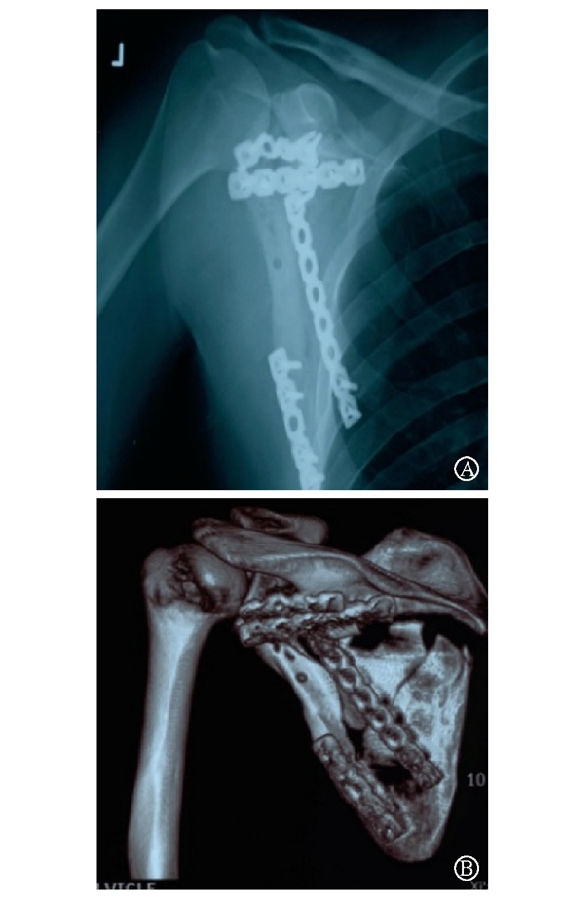

术前设计采用跨骨折区域钢板螺钉固定(图13)。术中可见纵向骨折区域骨质薄弱,骨折粉碎严重,钢板放置位置有限,操作极其困难(图14)。术中采用多块接骨板跨骨折区域固定,术后X线片及三维CT重建显示复位满意(图15)。针对此病例,如果采用缝线辅助固定技术,可使手术操作过程简化,达到同样的固定效果(图16)。

图15 术后X线片及CT三维重建示骨折复位满意,内固定位置良好 图A:术后X线片;图B:术后CT三维重建